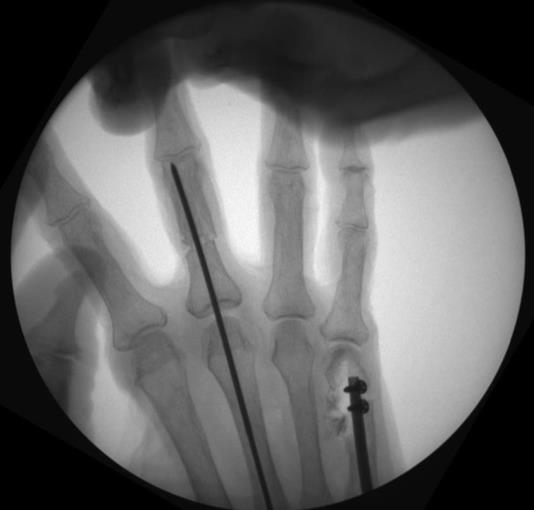

• place the k-wire tip into the cupped front end of the nail and advance the nail into the medullary canal while allowing the k-wire to exit

• confirm fracture reduction and final nail position with fluoroscopy, ensuring the locking screw holes are not near fracture lines

• retighten the drill guide locking screw after nail insertion

• insert a 1.4mm k-wire through the drill guide hole that is 5mm greater than the chosen nail length for distal provisional fixation

• insert a 1.4mm k-wire through the most proximal drill guide hole for proximal provisional fixation